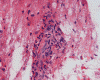

Panel A to E are MR images. Panel F and G are taken from intraoperative cytologic preparation. Panel H to M are taken from frozen section. Panel N and O are from paraffin section. These sections are stained by hematoxylin-eosin stain. Panel P is immunohistochemistry for neurofilament proteins. Panel Q is stained by Luxol fast blue-Periodic acid Schiff (LFB-PAS) stain.

The segment of spinal cord at T3-T4 level is expanded and is accompanied by edema that runs from T2-T6. The expansion and edema is roughly symmetrical along the long axis of the cord. The expanded levels are isointense to the white matter of the spinal cord on T1-weighed images (Panel A). The edema is best demonstrated on T-weighed images (Panel B, C, and E). Patchy and poorly defined enhancement is demonstrated in the expanded areas (Panel D). The remaining levels of the spinal cord and the brain are free of abnormal changes.